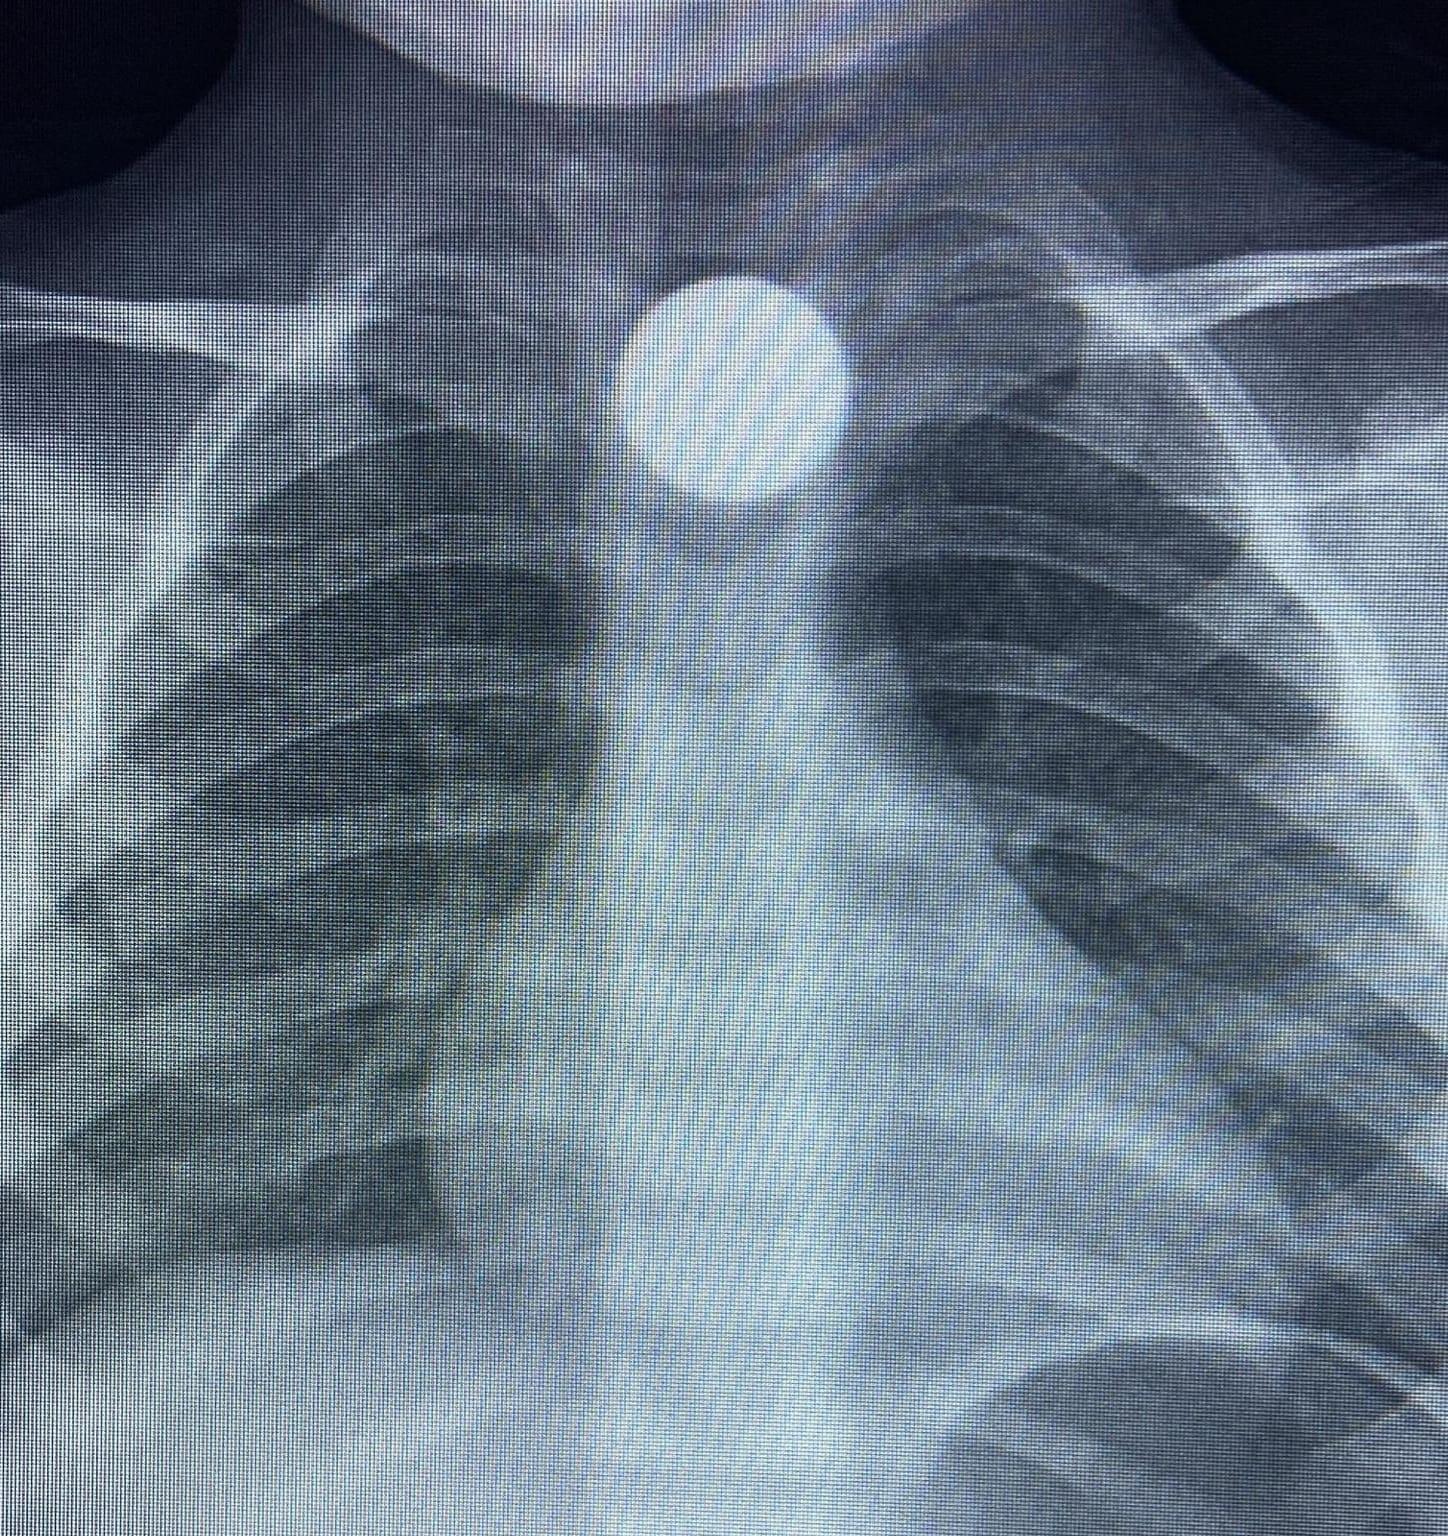

Yavuz YILMAZ/İNEGÖL (Bursa), (DHA)- BURSA’nın İnegöl ilçesinde evde bulup yuttuğu 50 kuruş madeni para yemek borusunda takılı kalan Bilal K. (3), hastanede tedaviye alındı.

Olay, kırsal Yeniceköy Mahallesi’nde meydana geldi. Bilal K., evde oynarken yerde bulduğu 50 kuruş madeni parayı ağzına alıp yuttu. Durumu fark eden ailesi, Bilal K.’yi özel araçla İnegöl Devlet Hastanesi’ne götürdü. Hastanede yapılan kontrollerde, madeni paranın Bilal K.’nin yemek borusunda takılı kaldığı belirlendi. Burada ilk müdahalesi yapılan Bilal K., daha sonra ambulansla Bursa Yüksek İhtisas Eğitim ve Araştırma Hastanesi’ne sevk edildi.